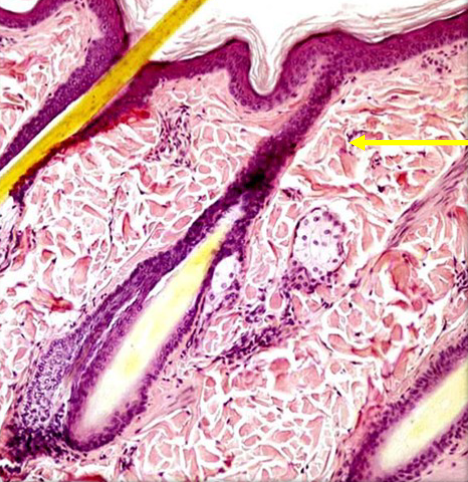

Epidermis

<p>The outermost layer of skin, composed of stratified squamous epithelium that provides a protective barrier against environmental factors. </p>

Dermis

<p>The layer of skin located beneath the epidermis, consisting of connective tissue that provides strength and elasticity, containing blood vessels, nerves, and hair follicles. </p>

Hypodermis

<p>The deepest layer of skin, also known as subcutaneous tissue, composed of loose connective tissue and fat, providing insulation and cushioning for underlying structures. </p>

95

Arrector pili muscle

<p>A small muscle located at the base of hair follicles that contracts in response to cold or fear, causing the hair to stand upright, also known as "goosebumps." </p>

Sebaceous oil glands

<p>Glands in the skin that secrete an oily substance called sebum, which helps to lubricate and protect the skin and hair. </p>

Sudoriferous sweat glands

<p>Glands that produce sweat to regulate body temperature and eliminate waste. </p>